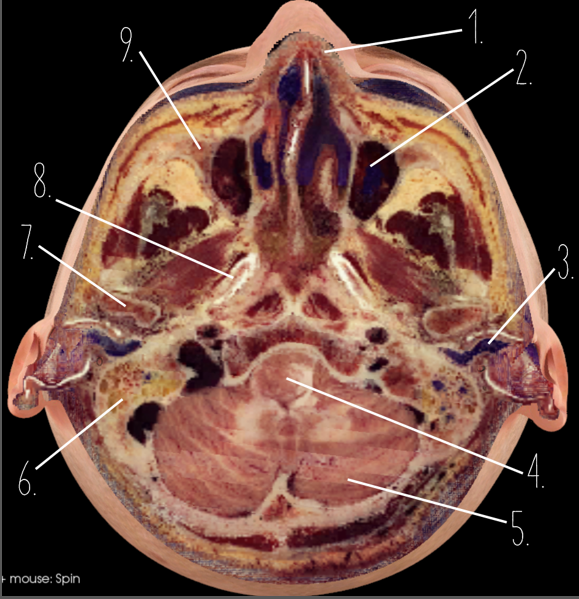

1?

Nasal Bone

2?

Maxillary Sinus

3?

External Acoustic Meatus

4?

Pons

5?

Cerebellum

6?

Mastoid Air Cells

7?

Mandibular Condyles

8?

Sphenoid Bone

9?

Maxillary Bone